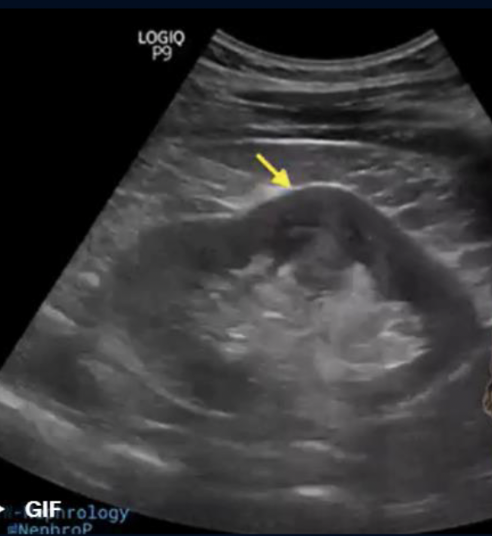

What is this?

Extrarenal Pelvis